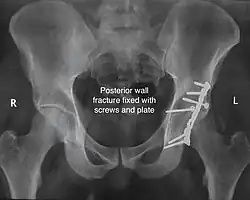

Posterior wall fracture fixed with screws and plate

The final management depends on the size of the fragment(s), stability and congruence of the joint. In some cases traction for six to eight weeks may be the only treatment required; however, surgical fixation using screw(s) and plate(s) may be required if the injury is more complex. The latter treatment will be called for if bone fragments do not fall into place, or if they are found in the joint, or if the joint itself is unstable.

Implants : normally lag screws and reconstruction plates are preferred implants